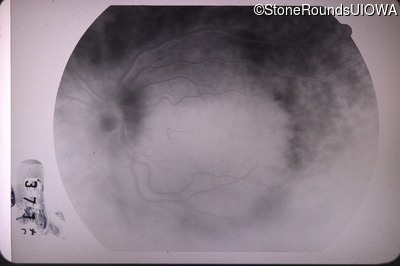

Fluorescein Angiography - Right - 20/40 -2

Exemplar